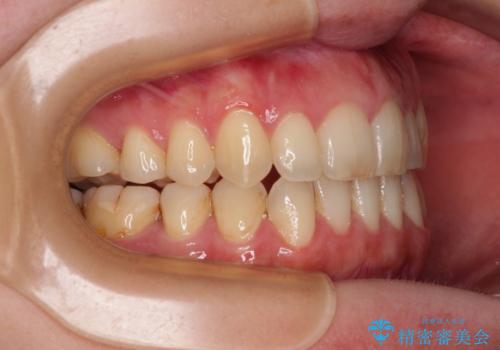

- 上下前歯の隙間を気にして来院された患者様です。

下顎前歯が1本欠損しており、上下小臼歯はクロスバイトとなり、上下前歯の接触もないという不正咬合の状態でした。

クロスバイトはワイヤー矯正が得意とするところであり、上下前歯の非接触や開咬はインビザラインの得意とするところであるので、ワイヤー装置により事前にクロスバイトを改善し、その後にインビザラインにて仕上げていくこととしました。

奥歯の咬み合わせに問題がある場合、インビザラインでは改善できないことが多々あります。事前にワイヤー装置により問題点を解消しておくことで、スムーズにインビザラインでの矯正治療を進めていくことができます。